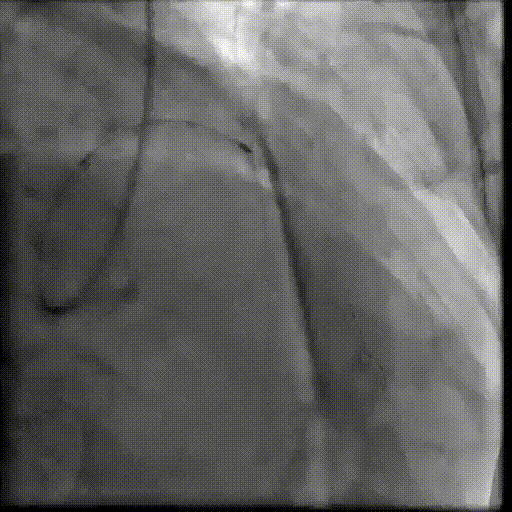

术中,杨征手术团队首先处理冠状动脉问题。造影结果显示,患者的冠脉血管不仅堵塞严重,而且钙化非常坚硬,常规器械难以通过。团队立即采用冠脉内旋磨技术,根据病变特殊性,选择高速旋转的「偏心」旋磨头对钙化部位进行处理。

与传统的同心旋磨不同,偏心旋磨系统的磨头质心与旋转轴线不重合。这种设计使得旋磨头在自转的同时,还能沿血管内壁进行公转扩径运动,扩大治疗范围,降低手术风险。尤其适用于处理过去难以治疗的血管转弯处的重度偏心型钙化斑块,能让支架得到完全扩张,减少残余狭窄。

完成血管的旋磨处理后,精准地释放了支架,冠脉血流瞬间通畅。手术团队则立即转向主动脉瓣置换。